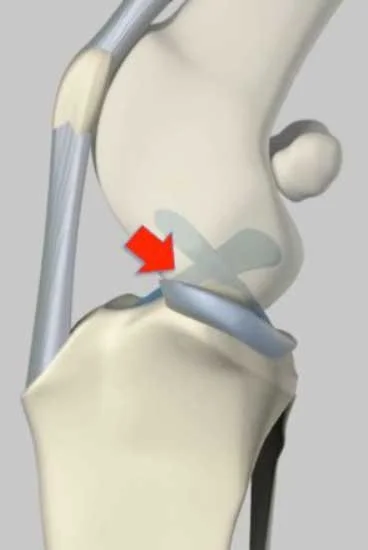

Cruciate ligament disease or injury

Cruciate ligament disease refers to damage or rupture of the cranial cruciate ligament within the knee (stifle) joint. This ligament plays a key role in stabilising the joint during movement. In the Cane Corso, cruciate injury may occur as a sudden traumatic event or develop gradually due to ligament degeneration. Left unmanaged, it can lead to pain, instability, and progressive arthritis.